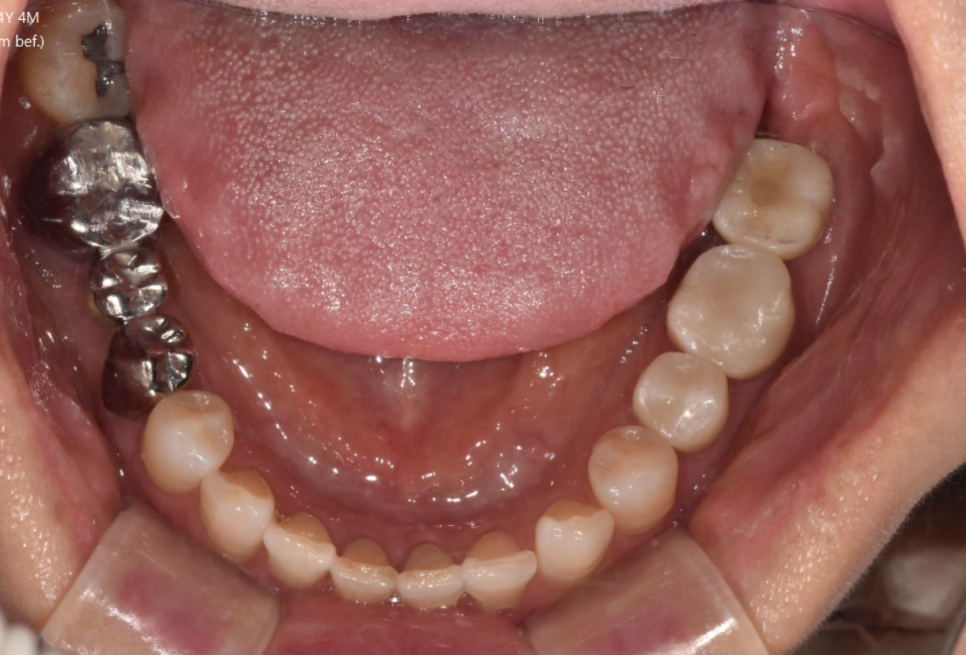

서울바르디치과에서는

최대한 자세히 알려드리기 위하여

사진을 찍어서 설명드립니다.

언제든지 사진이 필요하시면

말씀해주세요!!